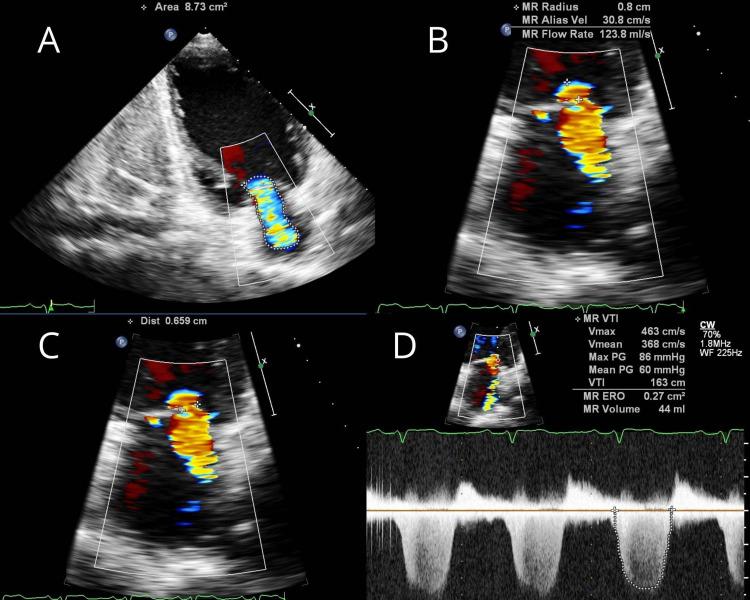

In infective endocarditis, the perivalvular abscess is a known complication with an incidence of more than 22%-29%, but the primary presentation of a healed aortic abscess without any clinical features of infective endocarditis is very rare. These sorts of cases are scarcely documented throughout literature. We present a successful surgical closure of healed perivalvular abscess cavity with aortic valve replacement and mitral valve repair.

在感染性心内膜炎中,瓣周脓肿是一种已知的并发症,发生率超过22% - 29%,但已愈合的主动脉脓肿在没有任何感染性心内膜炎临床特征的情况下首次出现是非常罕见的。这类病例在整个文献中鲜有记载。我们成功地通过主动脉瓣置换和二尖瓣修复对已愈合的瓣周脓肿腔进行了手术闭合。